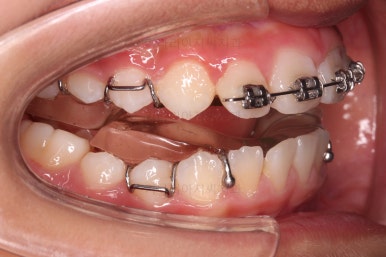

이번 치료를 위해 선택한 장치는 트윈블락(트윈블록, Twin block) 이라는 장치인데요.

위아래 뺐다꼈다하는 형태의 장치를 1년 ~ 1년 반 가량 껴주게 되면 아래턱의 성장이 이루어지며 교합이나 외모가 개선되는 장치입니다.

트윈블락 장치와 더불어 윗니 앞니는 가지런하게 하기 위해서 브라켓-철사 장치가 부분적으로 들어갔는데요.

아래턱이 성장하기 위해서 너무 삐뚠 윗니 앞니는 아래턱이 앞으로 나오는 걸 방해하기 때문에 부분적으로 부착형 장치를 쓸 수 밖에 없는 상황이었습니다.

윗니에 들어가는 장치는 악궁확장 기능도 들어가 있어서 위턱을 넓히며 아래턱을 앞으로 내어주는 3차원적인 조절이 가능했습니다.

점점 얼굴 모습이나 치열의 느낌이 달라지고 있고요.

아래턱이 앞으로 나와주면서 부정교합이 점점 개선되어가는 양상입니다.